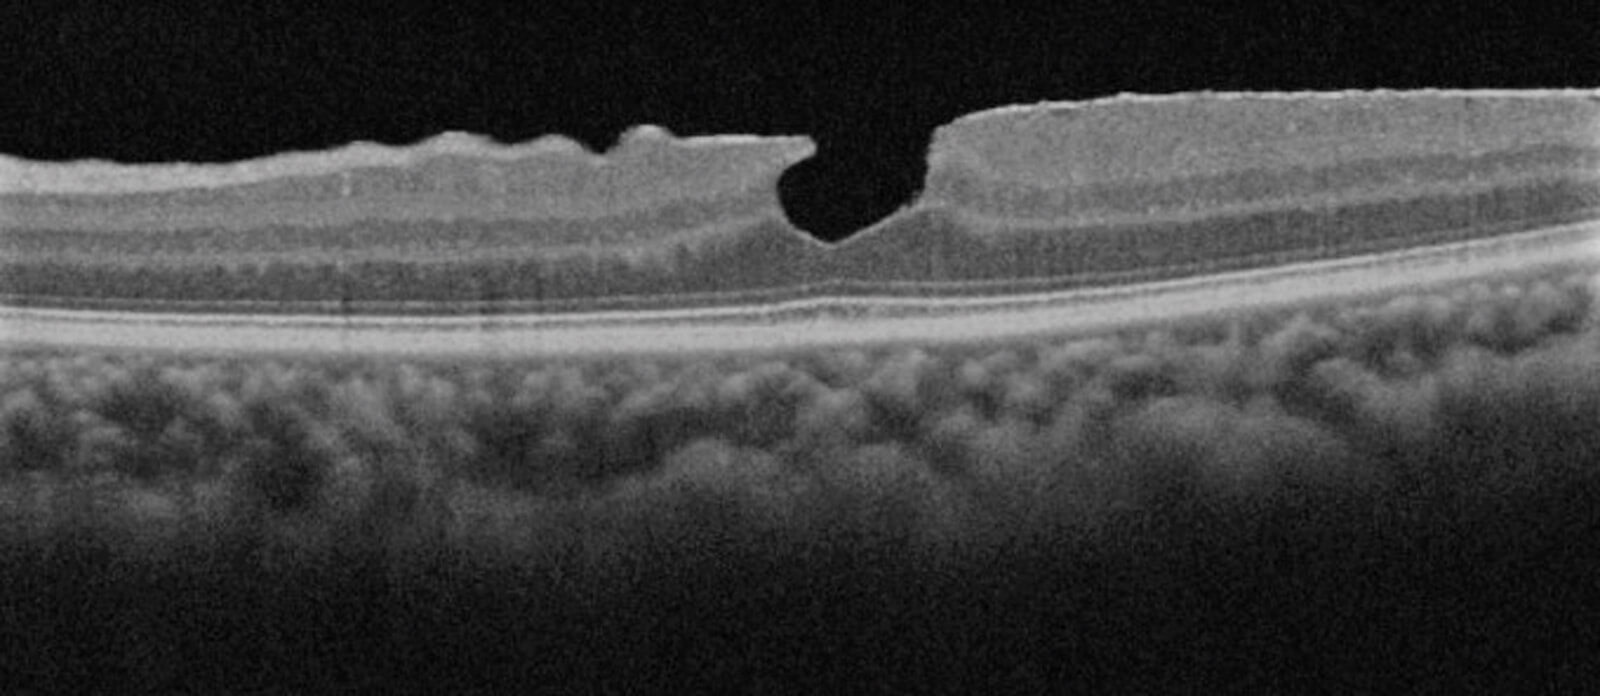

Figure 2: SD-OCT Scan of PH+ERM.

Lamellar macular hole (LMH): It is characterised by an irregular foveal contour and is often associated with an epiretinal membrane; a further visible feature is a split between the outer plexiform layer and the outer nuclear layer.

Pseudo-macular hole (PH): There is no interruption of the retinal layers instead present in the macular hole. The similarity is given by the alteration of the foveal profile usually caused by an epiretinal membrane or by a traction syndrome.